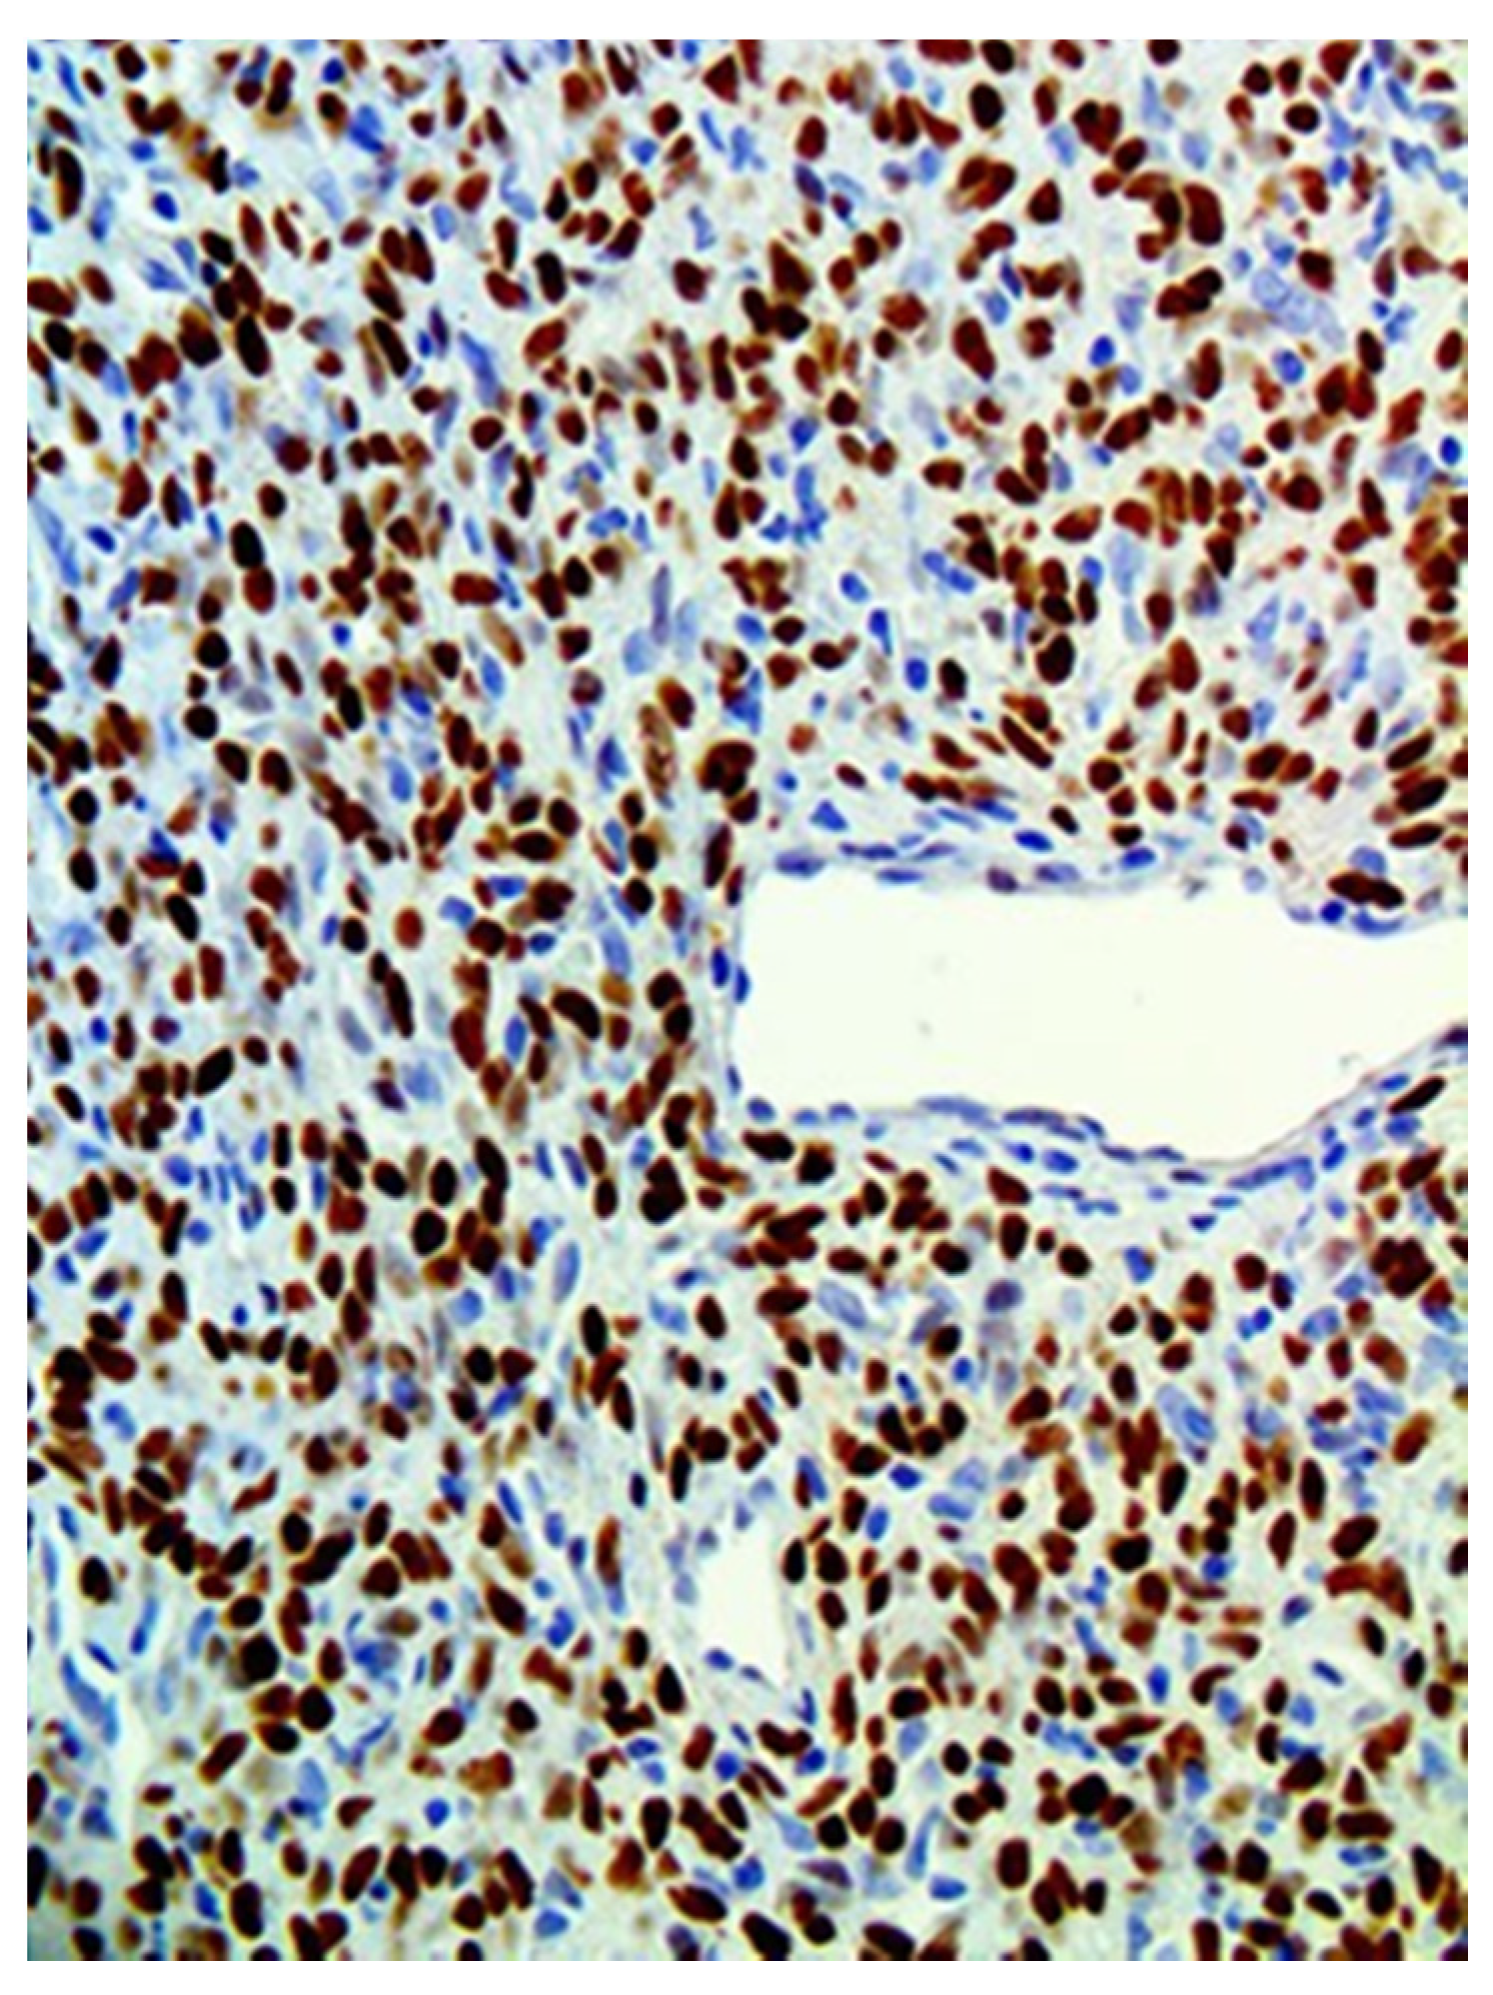

In immunohistochemical analysis, tumor cells were stained for CD34, CD99, and Bcl2. All cases were also positive for STAT6 (Figure 3, Figure 4, Figure 5, Figure 6 and Figure 7). Table 2 shows immunohistochemical staining for each patient. None of the cases included showed any overt atypia or mitotic activity, suggesting a benign behavior of all reported cases in this series.

Figure 7. STAT6 stains strongly and diffusely the nuclei of the tumor cells, a pathognomonic finding in SFT.